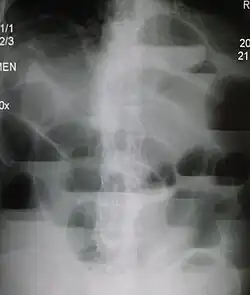

Radiological signs of bowel obstruction include bowel distension (small bowel loops dilated >3 cm) and the presence of multiple (more than 2) air-fluid levels on supine and erect abdominal radiographs.[16] Ultrasounds may be as useful as CT scanning to make the diagnosis.[17]

Small bowel obstruction on ultrasound[19]

-